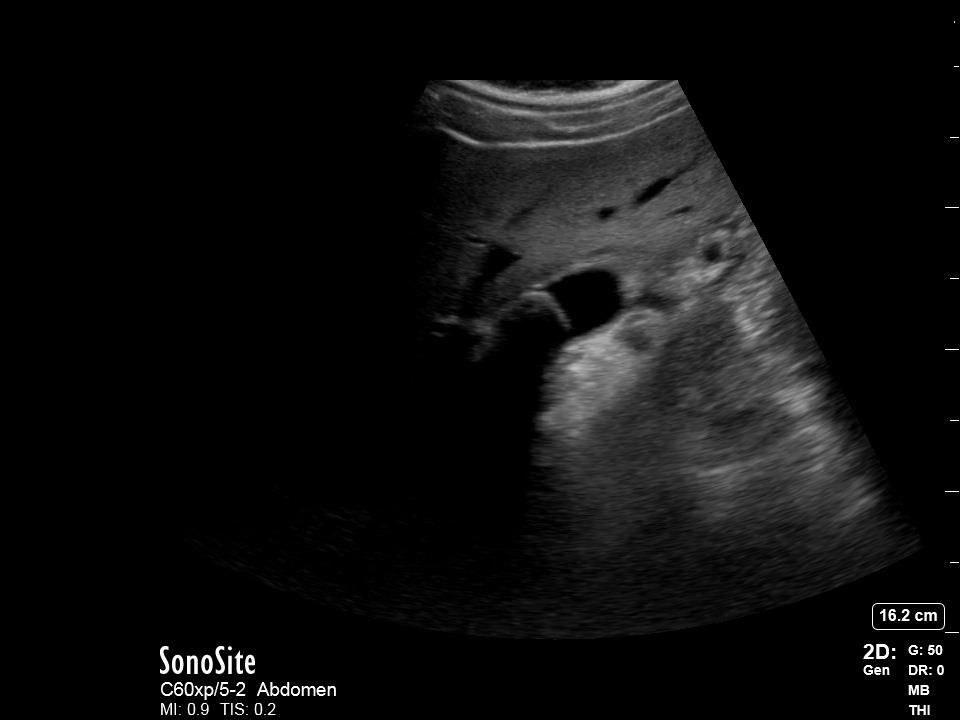

Cas4 : Patient à l’ambulatoire avec forte douleur HCD depuis 10jours. Cholécystite avec vésicule de densité homogène au foie secondaire à la boue biliaire.

Cas4_Clip1 démontre une vésicule biliaire distendue, avec multiple calcule au niveau du col et une bile entièrement transformée en boue biliaire. En raison de l’échotexture de la vésicule, il est donc facile de tout simplement ne pas la trouver…